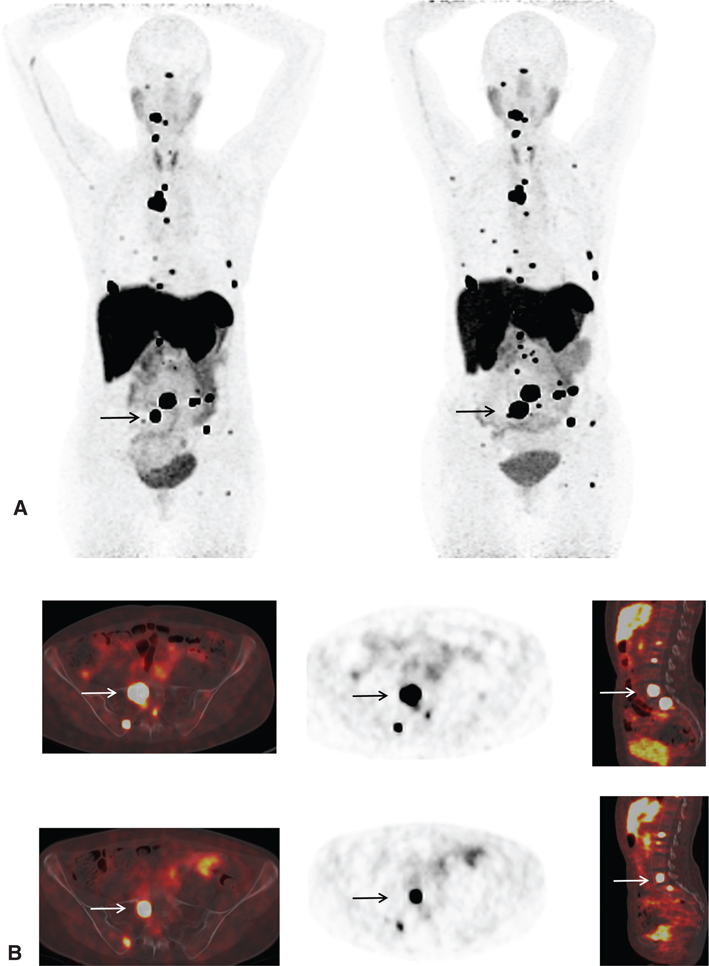

SPECT/CT improves sensitivity and specificity (Figure 6); in one case series, MIBG SPECT/CT was shown to increase diagnostic certainty in 89% of discordant CT and planar MIBG cases (41, 42).

Fig 6

Figure 6 A 40-year-old male patient with elevated catecholamines. (A) Whole body planar images, (B) coronal and axial attenuation-corrected SPECT images, and (C) axial non-enhanced CT and fused SPECT/CT images of the right adrenal region demonstrate a 4 cm × 3 cm × 4 cm soft tissue lesion with intense I-123 MIBG uptake much greater than hepatic uptake consistent with a biopsy-proven pheochromocytoma.